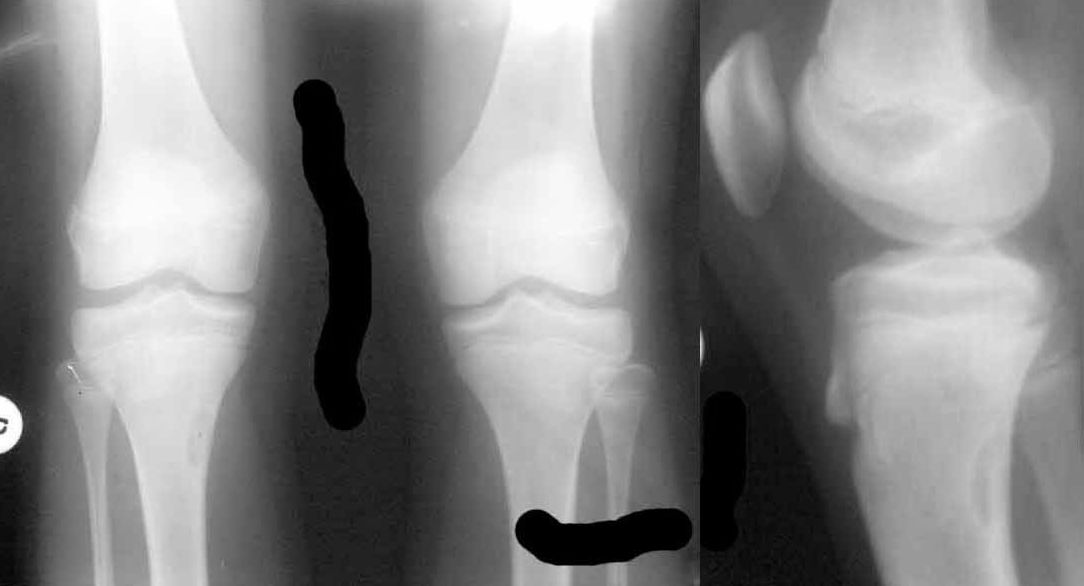

очаг фиброза в правой большеберцовой кости |

"Девочке сейчас 12.5 лет. Летом этого года стартовал пубертат, начала вытягиваться.

В течение лета были активные физические нагрузки, в августе - длительные пешие походы в горах. С сентября стали появляться боли в коленных суставах, связанные с подъемом по лестнице и при приседании. Боли непостоянные, то в одной, то в другой ноге, иногда одновременно в обоих коленях. В покое и при обычной ходьбе боли не отмечаются.

18.01.2011 сделали снимки коленных суставов - выявлен очаг фиброза в правой большеберцовой кости?"

Что это?